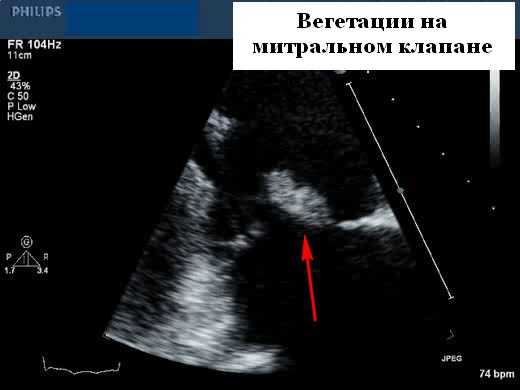

Вегетации из-за инфекционного эндокардита являются потенциально важными источниками эмболии, поэтому при подозрении необходимо проводить эхокардиографию. Как правило, у пациента в анамнезе есть рецидивирующая лихорадка и конституциональные симптомы, а также возможный провоцирующий фактор (недавняя стоматологическая или другая инвазивная процедура). Первичная идентификация вегетаций во время оценки потенциального источника эмболии становиться вероятной, поскольку диагноз обычно подозревается клинически. Таким образом, большая часть вегетаций выявляется на эхокардиографии до того, как возникают серьезные эмболические осложнения.

Эхокардиографические особенности при инфекционном эндокардите

Вегетации имеют ряд типичных эхокардиографических характеристик, и диагноз обычно может быть установлен с относительно высокой степенью уверенности с помощью эхокардиографии в сочетании с клинической симптоматикой. Они кажутся менее отражающими (серыми) по сравнению с нормальной тканью клапана и расположены перед клапаном на линии струи регургитации (предсердная поверхность митрального клапана и поверхность желудочков створок аорты). Обычно они выглядят дольчатыми с неровными, плохо очерченными границами и имеют хаотическое движение, в отличие от других клапанных образований (фиброэластомы и т. д.), которые имеют тенденцию к более высокому отражению, с четко определенными границами и менее хаотичным движением. Тонкие протяженные клапанные прикрепления с узким основанием, скорее всего, будут неинфекционными фибринозными нитями, чем вегетациями. Признаки, которые помогают отличить вегетации от других образований, включают наличие разрушения створки, регургитации клапана и образования абсцесса или свища. Сообщается, что чувствительность трансторакальной эхокардиографии для выявления признаков эндокардита составляет от 44 до 60%, по сравнению с чувствительностью 88 и 100% для ЧПЭхоКГ. Мелкие вегетации ( 90%), хотя при более высоком разрешении чреспищеводной эхокардиографии повышенная чувствительность может происходить за счет немного сниженной специфичности (возможность маркировать небольшие доброкачественные фибринозные тяжи на нативных и протезных клапанах или незначительно подвижные шовный материал на протезах клапанов в виде мелких нитей).

Факторы, связанные с эмболией вегетациями

Риск эмболизации, связанной с вегетацией, варьируется в широких пределах (17-50%). Факторы, связанные с риском эмболии, включают их размер, подвижность и временные изменения размера вегетаций. Наиболее важным эхокардиографическим признаком, который позволяет прогнозировать риск эмболии, является размер вегетации. Если они размером> 10 мм, то имеют значительно более высокую частоту эмболических событий по сравнению с более мелкими вегетациями (47% против 19%). Увеличение или отсутствие изменений вегетации после 4-8 недель терапии связано с увеличением частоты эмболических событий (45% против 17%). Вегетации на митральном клапане имеют более высокий риск эмболии. Некоторые микроорганизмы связаны с образованием более крупных вегетаций, включая Staphylococcus aureus и группу организмов HACEK. Несмотря на адекватную антибактериальную терапию, вегетации могут стать организованными и сохраняться, и эти остаточные поражения с гораздо меньшей вероятностью будут давать эмболию.